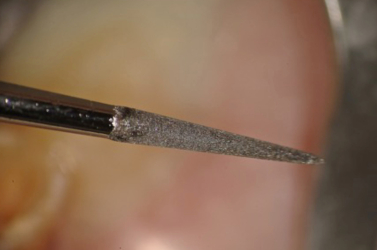

TUFI® #1 Ultrasonic Tip (San Diego Swiss Dental Machining)

Tip Placed on GP Dry to Remove Coronal Portion of GP Easily